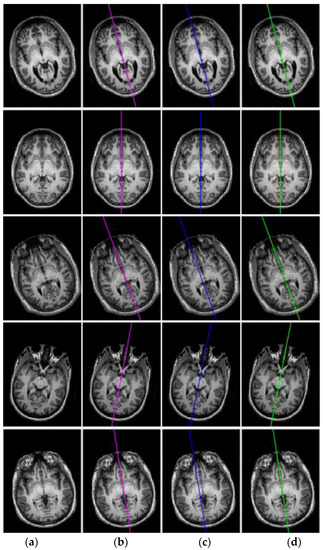

Visual comparison of the proposed algorithm with Ruppert et al. algorithm for extracting the symmetric axis (MSP) from perfectly symmetric datasets: (a) input slice, (b) ground-truth slice, (c) Ruppert et al. [27] algorithm results, and (d) proposed algorithm results.

To precisely inspect the accuracy of the proposed algorithm, many illustrative slices orthogonal to the estimated MSP are displayed in Figure 11. The lines in different colors (magenta, blue and green) are the intersecting lines between the extracted MSP and the respective orthogonal slice. The first column represents the input images and the second column shows the input images with the GT MSP intersection line (magenta color line). Similarly, third and fourth columns contain the images of Ruppert et al. and proposed algorithm results, respectively. Visual comparison in Figure 11 also reveals that the proposed algorithm outperformed Ruppert et al. algorithm in terms of accuracy, both in orientation and offsets. Ruppert et al. algorithm could not always achieve a rigorous estimate of MSP, particularly when the brain MRIs underwent a considerable transformation (rotation, translation, noise).